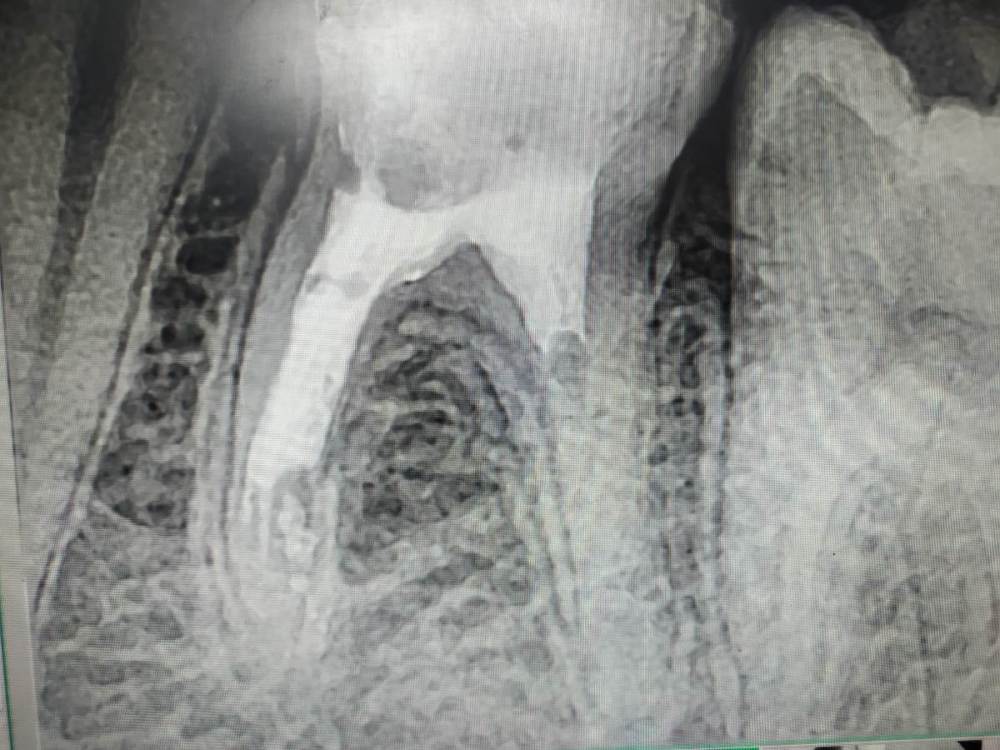

неа, силер после гх продавливается только на такую глубину

post-56770-0-58474200-1583323033_thumb.jpg